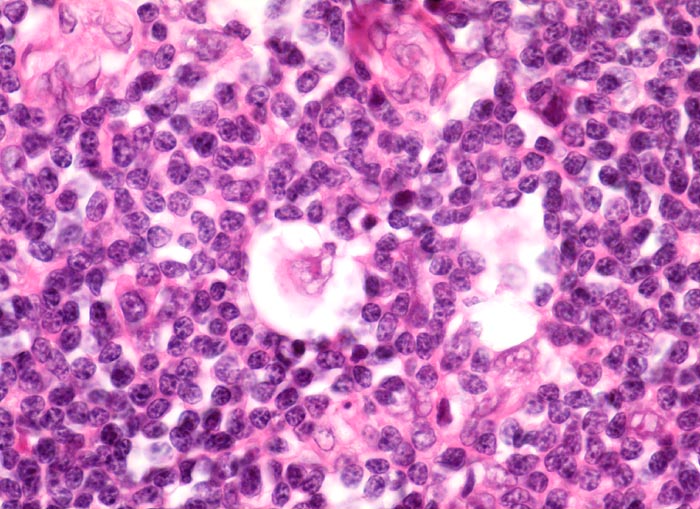

• Reed-Sternbergzelle mit spiegelbildlich angeordneten Kernen mit sehr grossen eosinophilen Nukleolen.

• Einkernige Hodgkinzelle mit prominentem Nukleolus umgeben von einem Retraktionsartefakt (Lakunarzelle).

• Die Knoten bestehen vorwiegend aus einem Mischzellinfiltrat reaktiver Zellen: Lymphozyten, Histiozyten, eosinophile Granulozyten und Plasmazellen.